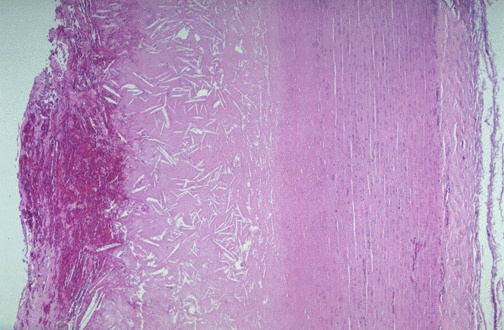

| This microscopic cross section of the aorta shows a large overlying atheroma on the left. Cholesterol clefts are numerous in this atheroma. The lumenal surface on the far left shows ulceration and hemorrhage. Despite such ulceration, atheromatous emboli are rare (or at least, complications of them are rare). |